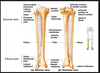

tibia